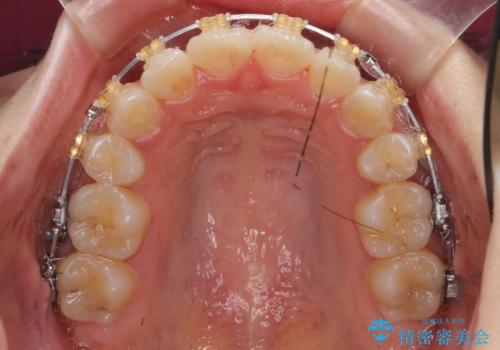

八重歯の治療 仕上がり重視で

- 八重歯を主訴に来院。

仕上がり重視とのことで、小臼歯を抜歯し、スタンダードな治療方法で仕上げています。

上下の小臼歯を抜歯しています。

矯正用インプラントアンカーを使用してしっかり前歯を下げたため、口元が大きく改善しています。